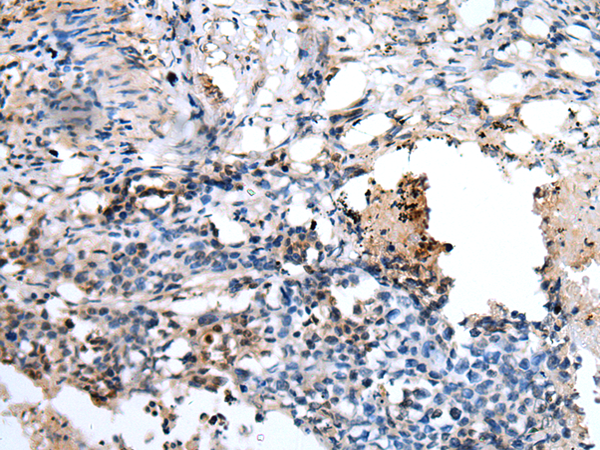

IHC positive control: |

Human lung cancer |

IHC Recommend dilution: |

30-150 |